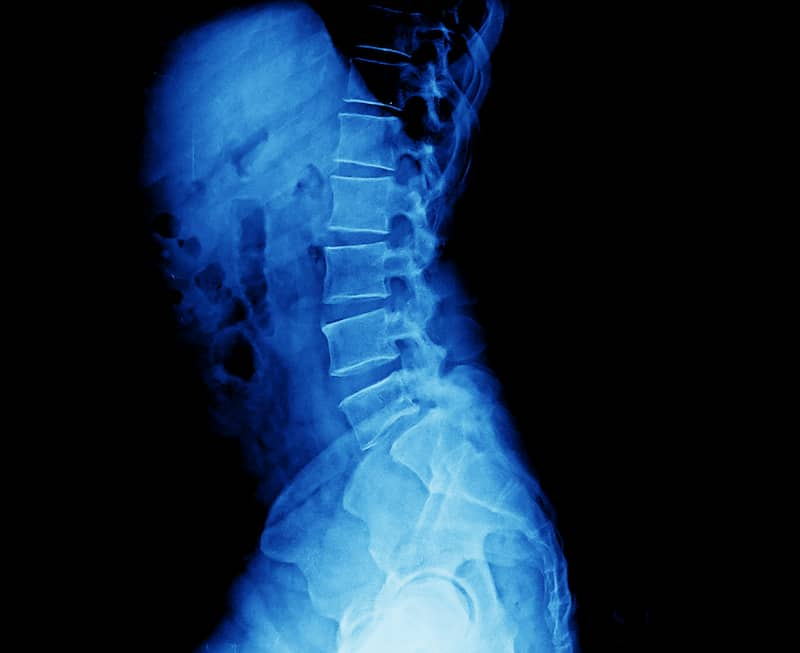

4. You are not your scan result.

Scans are important, but normally only for the minority of people. Despite what most people might think, scans cannot show you your pain or why things might be stiff or why you can’t bend forwards without being in pain. They are simply a picture on a particular day at a particular time. They are very good at showing you what you look like on the inside, but not always why something is sore. Scan results also often come with long, complicated, scary-sounding names and phrases that can sometimes sound concerning but often are simply medical terminology to describe things that are normal or should be there.

An effective assessment will take into account all aspects of you and your life when considering why something is sore. Understanding your strength, your movement, your confidence or trust in your back and what it can do, along with things like your sleep quality, expectations, impression of what’s going on and belief/values regarding back pain, are all considered to be vitally important when working with someone with pain. All of this means that you are not just a scan result and shouldn’t be considered so.